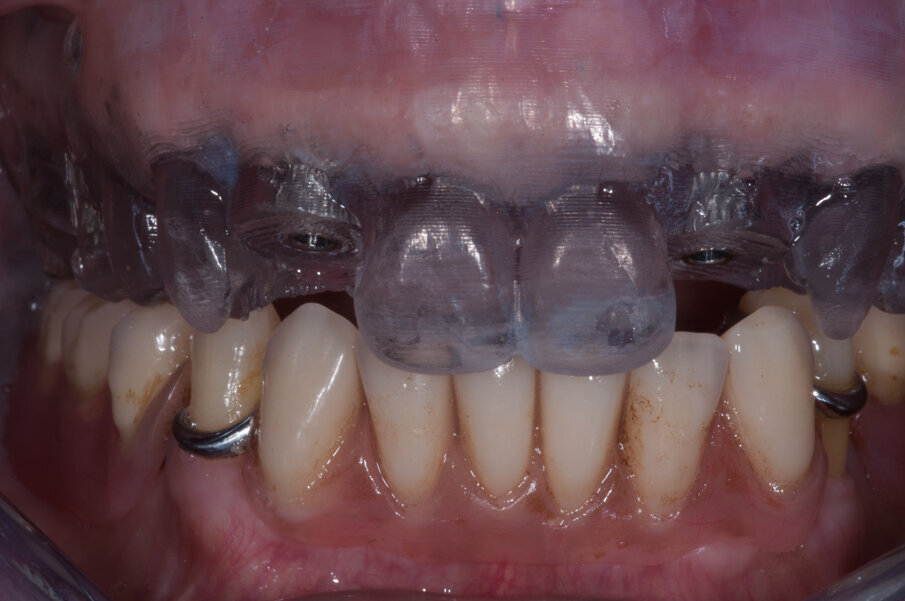

Grazie a questo tipo di pianificazione il software produce una guida chirurgica che viene stampata da una stampante 3D e consente al chirurgo di operare con tecnica “flapless” cioè senza la necessità di aprire dei lembi e causare un maggiore traumatismo al paziente. La guida chirurgica trasparente viene provata in bocca al paziente prima dell’intervento chirurgico per testare la sua stabilità e precisione nel rapporto con i tessuti molli (Figg. 20, 21). In questo caso specifico si era pianificato di utilizzare un nuovo approccio con degli impianti e componenti protesiche particolari, la tecnica “Smart fix” di Astra Tech Implant (Dentsply Sirona) (Figg. 22-25).